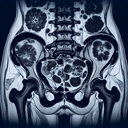

МРТ органів малого тазу

Магнітно-резонансна томографія (МРТ) органів малого тазу – це неінвазивний метод діагностики, який використовує магнітні поля та радіохвилі для створення детальних зображень органів та структур в цій зоні. ### Покази до проведення МРТ: - Підозра на пухлинні утворення - Діагностика та моніторинг захворювань матки, яєчників у жінок - Оцінка простати у чоловіків - Вивчення стану тазових кісток, сечового міхура - Оцінка запальних процесів ### Підготовка до МРТ: 1. **Консультація з лікарем:** - Повідомте про наявність імплантатів, наявність кардіостимулятора, протезів чи інших металевих предметів у тілі...